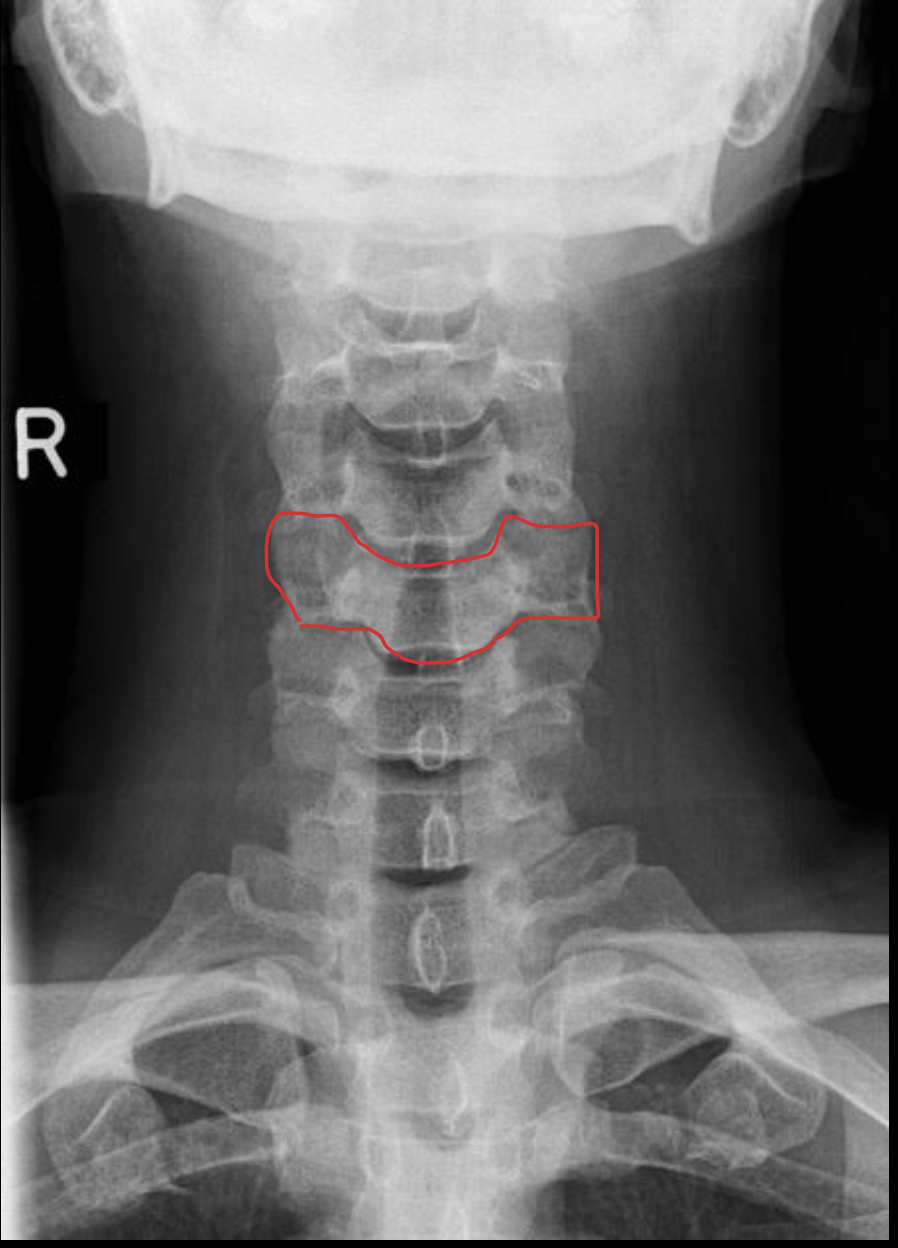

c5

c6

c7

T1

1ST Rib

钩突

Uncinate process

关节柱 / 侧块

Articular pillars

棘突

Spinous process